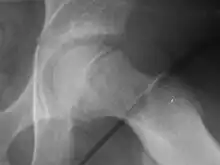

X-ray showing a slipped capital femoral epiphysis, before and after surgical fixation.

The diagnosis requires x-rays of the pelvis, with anteriorposterior (AP) and frog-leg lateral views.[11] The appearance of the head of the femur in relation to the shaft likens that of a "melting ice cream cone", visible with Klein's line. The severity of the disease can be measured using the Southwick angle.